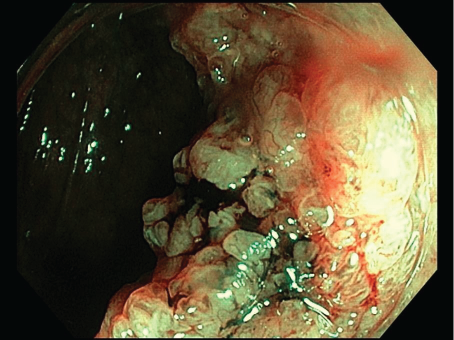

Trong quá trình nội soi, bác sĩ đã phát hiện tổn thương LST-G nodular mixed với kích thước khoảng 50mm tại vị trí manh tràng trên nền đa polyp đại tràng. Nội soi với NBI đánh giá tổn thương cấu trúc biểu mô bề mặt dạng tuyến ống, nhung mao, và mạch máu tương đối đồng nhất, khẩu kính không lớn, đọng nhiều dịch nhày và xuất tiết, đánh giá JNET Type 2A.